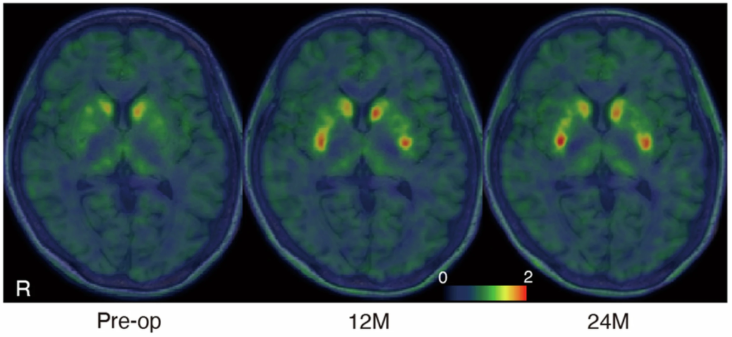

Bệnh Parkinson là một bệnh thần kinh tiến triển, do sự thoái hóa và mất đi của các tế bào não sản sinh dopamine, dẫn đến suy giảm chức năng vận động. Khác với các phương pháp điều trị bằng thuốc hiện nay chỉ tạm thời thay thế dopamine, Amchepry hướng đến khôi phục khả năng tự sản sinh dopamine của cơ thể. Trong một thử nghiệm lâm sàng giai đoạn I/II tại Bệnh viện Đại học Kyoto, 7 bệnh nhân được cấy ghép liệu pháp này vào não, sau đó theo dõi trong 24 tháng, chủ yếu tập trung vào đánh giá tính an toàn, kết quả phụ xác định hiệu quả của liệu pháp. Kết quả không ghi nhận tác dụng phụ nghiêm trọng, không hình thành khối u. Trong 6 bệnh nhân được đánh giá hiệu quả, 4-5 bệnh nhân có sự cải thiện về chức năng vận động, đồng thời tăng sự giải phóng dopamine trong não.

Fluorine-18-l-dihydroxyphenylalanine (18F-DOPA) được sử dụng để đánh giá quá trình tổng hợp dopamine. Hình ảnh bán định lượng 18F-DOPA được ghi nhận sau 80-90 phút tiêm thuốc, sự thay đổi màu sắc từ xanh đậm sang đỏ ở vùng nhân bèo hai bên cho thấy sự hấp thụ 18F-DOPA tăng lên, phản ánh sự tổng hợp dopamine bởi các tế bào được cấy ghép (Pre-Op: trước phẫu thuật, 12 M: 12 tháng, 24 M: 24 tháng).

Nguồn: Sawamoto N., et al. (2025). Phase I/II trial of iPS-cell-derived dopaminergic cells for Parkinson’s disease. Nature, 641(8064), 971-977. https://doi.org/10.1038/s41586-025-08700-0